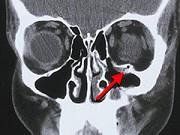

问题 某患者头面部被拳头击伤,做CT扫描如图,考虑诊断为 ( )

选项 A、眼眶内侧壁骨折 B、眼眶底骨折 C、眼眶外侧壁骨折 D、眼眶下壁骨折 E、眼眶上壁骨折

答案 D